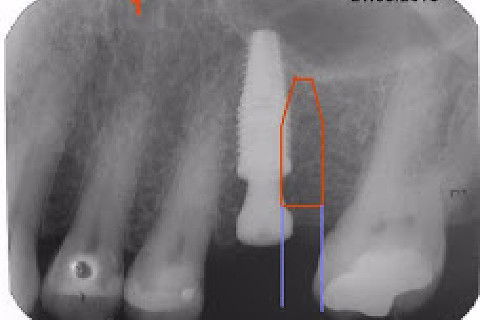

Instalação de um implante em região do 26. Utilizamos um implante cone morse Alvim Neodent 4.3 X 11,5. Foi uma cirurgia muito rápída e minimamente traumática, sem retalho e sutura.